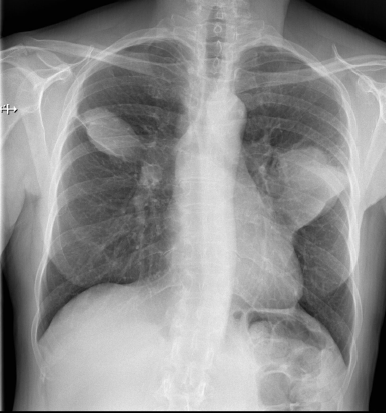

Dosimétrie en scanographie thoracique